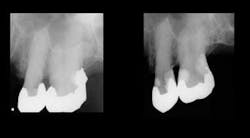

The most popular brands of RMGI restorative material are Ketac™ Nano from 3M ESPE, and FUJI II™ LC and FUJI Filling™ LC from GC (Figures 1 and 2). These materials have been used for restoration of highly caries–active patients such as bulimics, radiation–therapy patients, chemotherapy patients, or those with senile caries (Figures 3 and 4) with notable clinical success. Empirical evidence has convinced me of the cariostatic properties of the RMGI restorative materials.